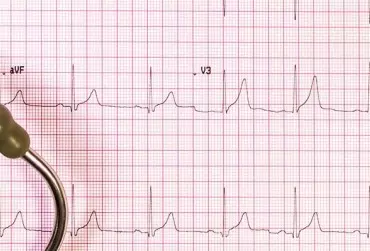

Rodzinnie występujący zespół wydłużonego QT. Opis przypadku